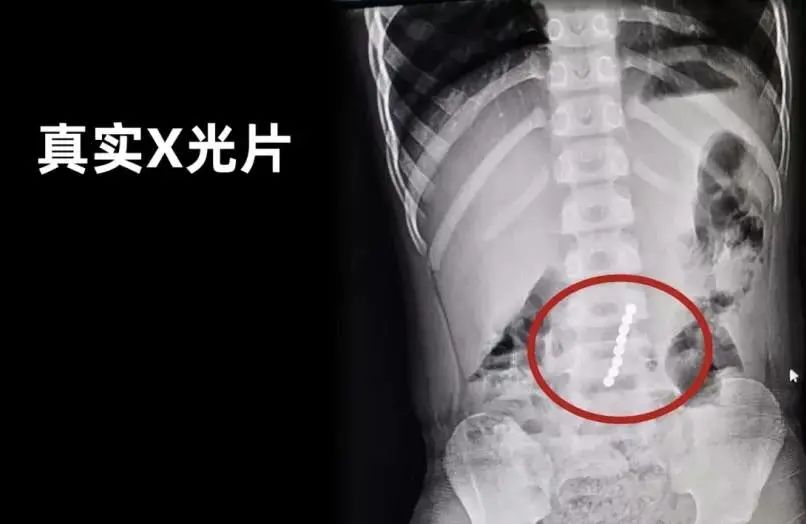

专家介绍,如果儿童吞食两个及两个以上的强力磁铁,或者吞食强力磁铁和其他磁性物体(铁、钴、镍),磁铁会在消化系统中与另一个磁铁(或铁磁性物体)吸附,并对肠壁产生压力。

简要说,就是磁力珠磁力强大,即使隔着肠道也能黏在一起,影响肠胃的正常蠕动,甚至挤压黏膜,导致黏膜缺血,严重时可能会造成肠梗阻,肠穿孔等。如果不小心误食或者塞入体内,想要取出来有的需要紧急做肠镜,有的则只能做开腹手术!

最可怕的是,磁力珠丢几个一时半会也发现不了,很可能延误了最佳治疗时间。